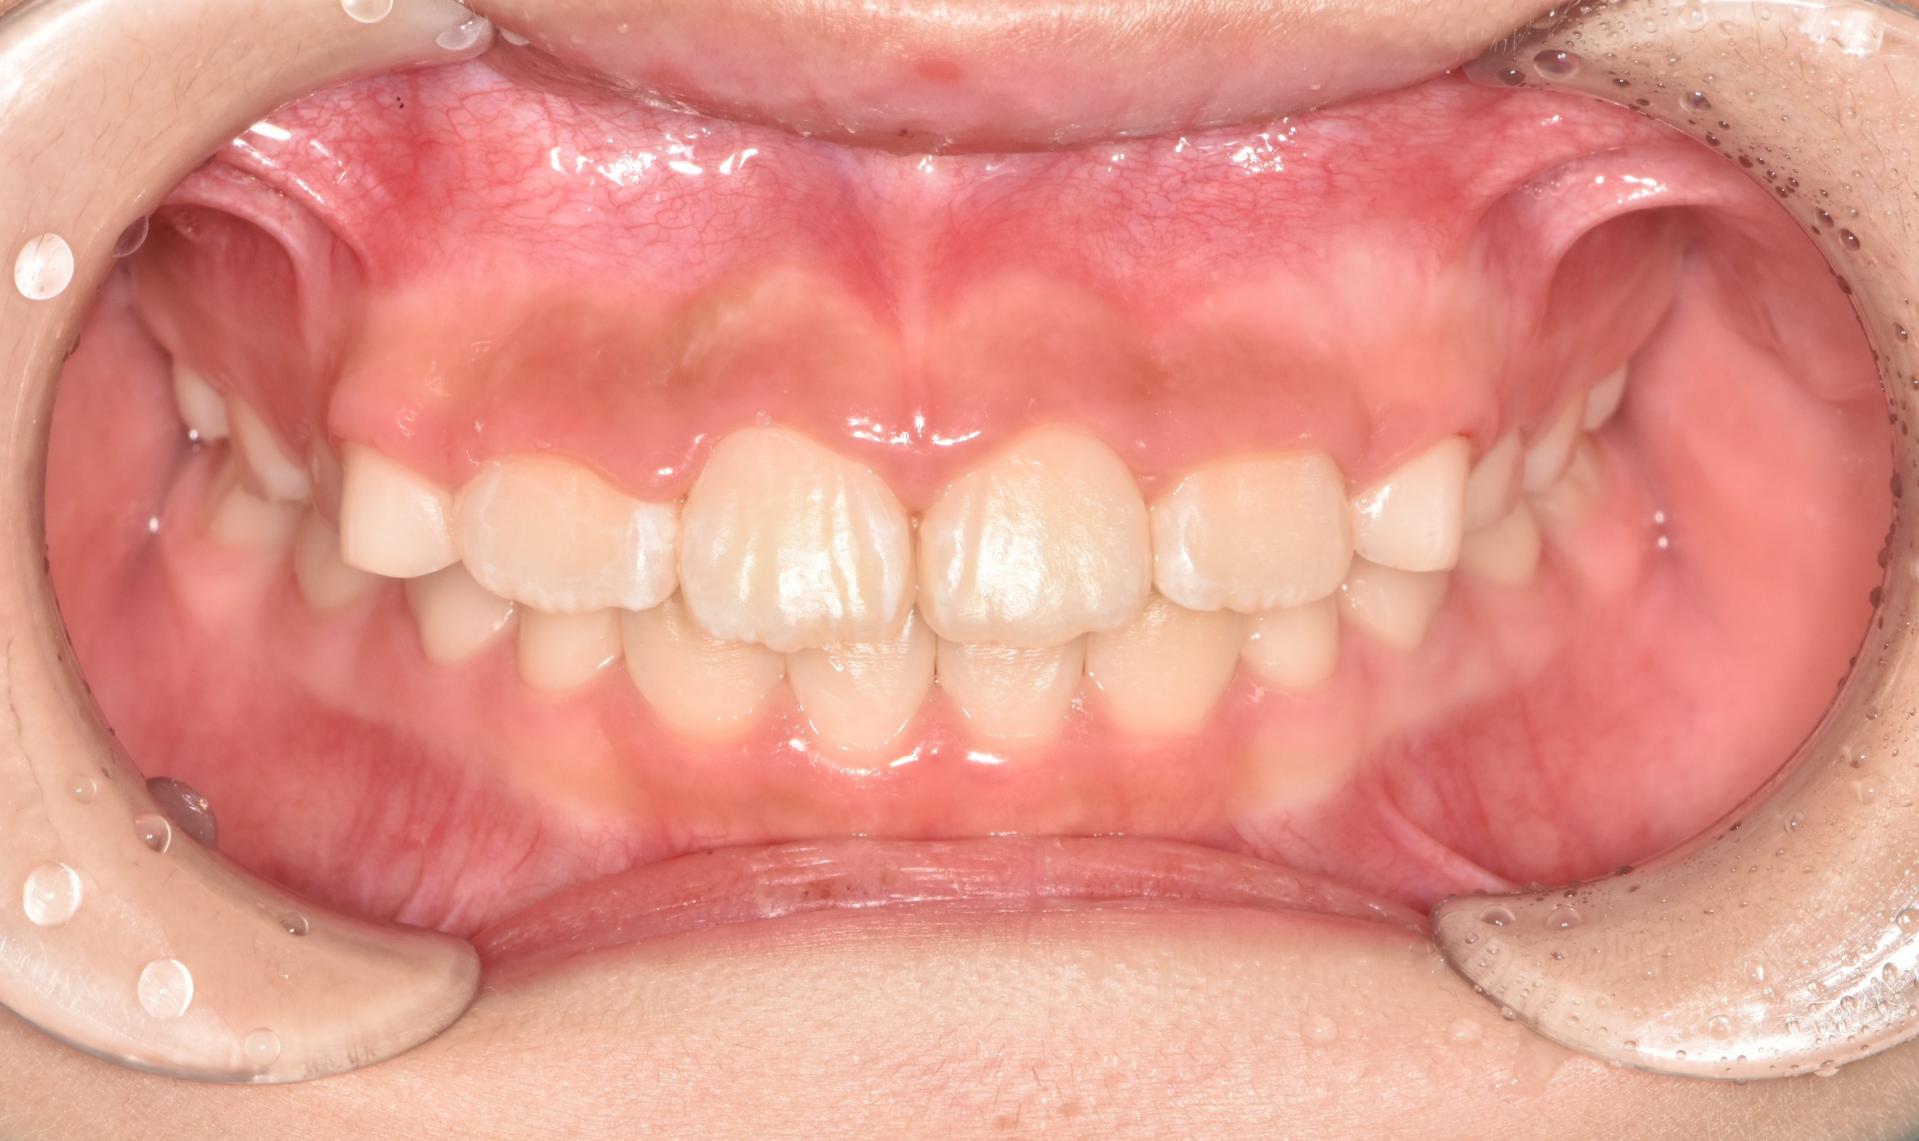

치료완료 후의 모습입니다. 앞니도 가지런해졌고, 좁았던 악궁이 넓어져서 추후 나올 송곳니, 어금니의 공간도 충분합니다.